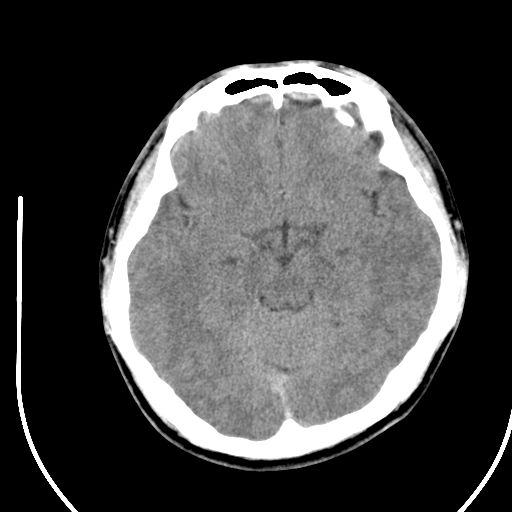

标题: CT28158:男,27Y。头痛数月,左顶叶血管瘤。 [打印本页]

标题: CT28158:男,27Y。头痛数月,左顶叶血管瘤。

考虑左顶叶海绵状血管瘤,建议mr检查。

左侧额叶海绵状血管瘤可能性大;建议行mri检查。

考虑血管畸形,因其周可见水肿,不除外感染性病灶。建议mri检查。